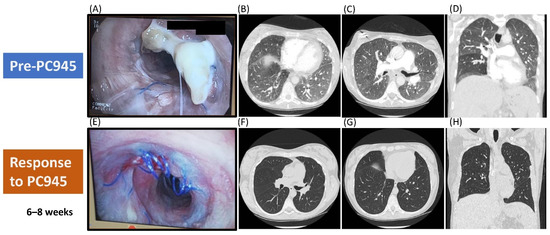

- Pagani, N.; Armstrong-James, D.; Reed, A. Successful salvage therapy for fungal bronchial anastomotic infection after -lung transplantation with an inhaled triazole anti-fungal PC945. J. Heart Lung Transplant. Off. Publ. Int. Soc. Heart Transplant. 2020. [Google Scholar] [CrossRef] [PubMed]